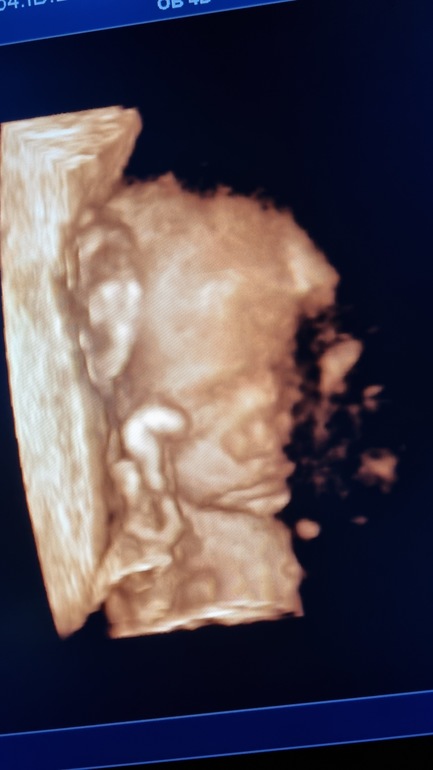

Сходила на 3д узи и обалдела от технологий 😍 абсолютно всё! видно - щёчки, губки,особенно носик папин 😄 как он загордился от этой новости, надо было видеть. Кстати если в жк хорошая узистка, рекомендую делать через них платно, намного дешевле, чем в частных.

А на 20 хорошо было видно? В плане на человечка похожа с щечками😄 мне строго рекомендовали в районе 24 идти, я даже не стала экспериментировать)